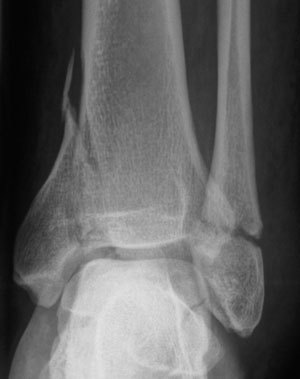

Q

Patient consulte aux urgences pour douleurs importantes de cheville et impotence fonctionnelle après une chute. Des radios sont faites: quel diagnostic? Quel est le mécanisme lésionnel probable?

A

Fracture bimalléolaire de cheville sous-tuberculaire

mécanisme en aDduction forcée